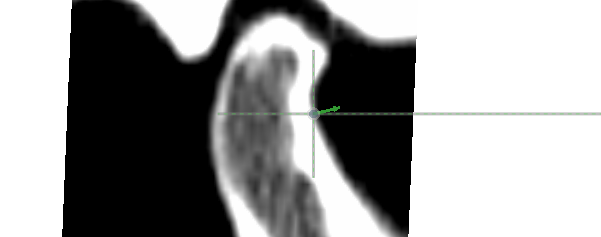

Adjusting Semi-Landmarks

- Rename the condyle patch under “Semi-landmark Group”.

- Drag the semi-landmark point in the slice window to adjust its position. The semi-landmark’s movement is restricted to the long dotted line.

- Move to the next semi-landmark with the right arrow key on the keyboard or the “>” button under “Semi-landmark”. Toggle a semi-landmark as missing by selecting a slice window or 3D window and pressing the “M” key or by clicking the “Mark as ‘missing’” check box.

- Once all semi-landmarks in the condyle patch have been adjusted, click the “<” or “>” button under “Semi-landmark Group”, and repeat the above process for the fossa.